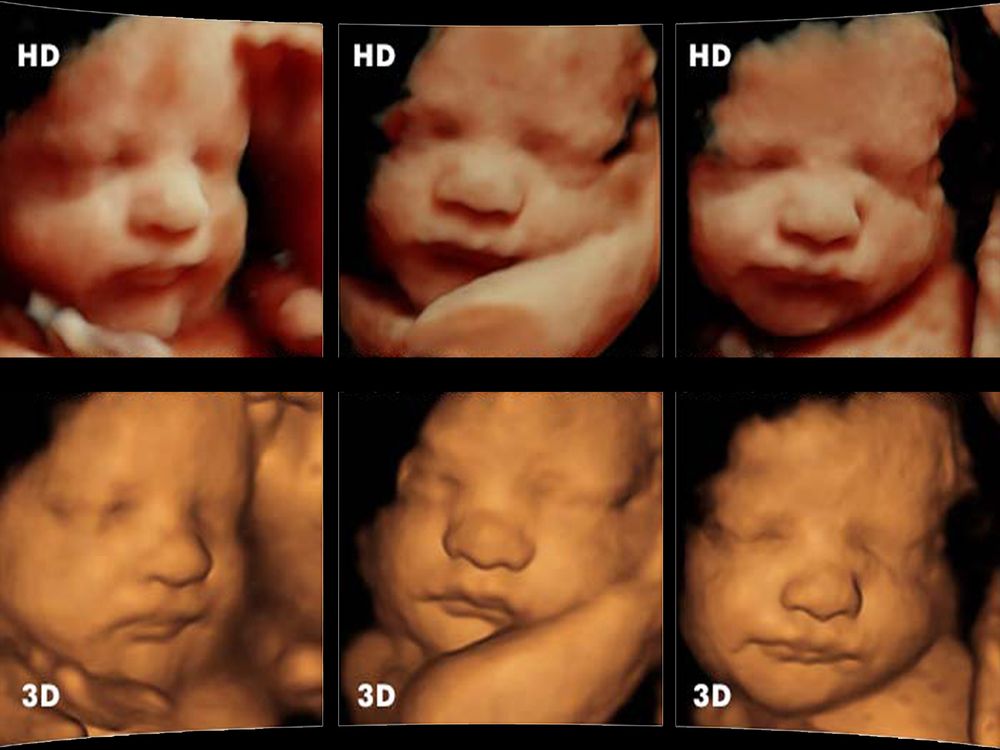

Preguntas frecuentes sobre ultrasonido 3D, 4D y HD

Las preguntas que se enumeran a continuación son las preguntas más frecuentes acerca de nuestros paquetes de Ultrasonido Prenatal Electivo 3D, Ultrasonido 4D y Ultrasonido HD. Si tiene alguna pregunta que no se responde a continuación, llámenos al 800 002 7646. Ofrecemos ultrasonidos prenatales opcionales en 2D, 3D y 4D para brindar una experiencia deSigue leyendo «Preguntas frecuentes sobre ultrasonido 3D, 4D y HD»